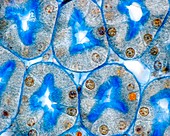

12420843 - Artery, TEM

12302981 - Artery, TEM